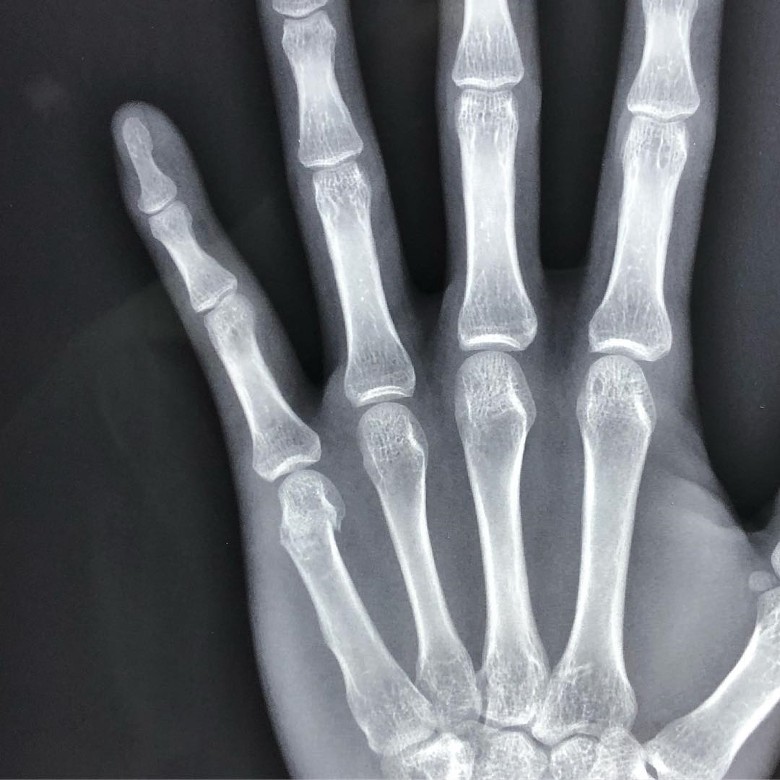

王浩信近期都在拍摄新剧《解决师》,里面有不少动作戏,所以很容易就受伤!他在社交平台上传了两张露“骨”照,透露有拍打戏时让尾指骨折。

他写道:“想和大家分享,经过这件事,我发现原来我在面对自己喜欢做的事情,痛都可以不理的行为并没有被岁月冲淡,就好像以前扭到脚第二天还可以去打篮球的热血,好像比以前更严重了。我真的很开心,因为我感到活着!为了庆祝这件事,就和大家分享一张入行以来最露骨的照片,鼓励大家要keep着这团火!“